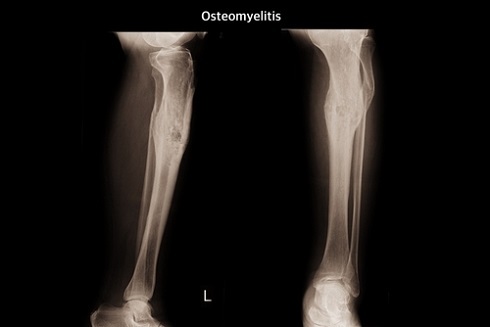

Хронический остеомиелит большеберцовой кости ⁠⁠

Остеомиелит — гнойно-некротическое заболевание, развивающееся в костном мозге, поражающее кости и окружающие их мягкотканые структуры. Существует несколько классификаций остеомиелита. По характеру течения выделяют: острый, подострый и хронический. В зависимости от механизма заражения: посттравматический и гематогенный.

Рентгенографическое исследование на ранних сроках позволяет выявить изменение плотности окружающих кость мягких тканей, участки деструкции костной ткани, периостит. На поздних сроках (начиная с 14-ого дня) на рентгенограммах определяются обширные очаги деструкции, линейные, слоистые периостальные наслоения, участки склероза вокруг секвестров и зон деструкции и окружающая эти участки зона остеопороза. В случае посттравматического остеомиелита определяется замедление консолидации отломков. Хронический остеомиелит на рентгенограммах проявляется гиперостозом (и, как следствие, деформацией кости), очагами деструкции кости, окружѐнными зоной склероза; секвестрами, остеопорозом.